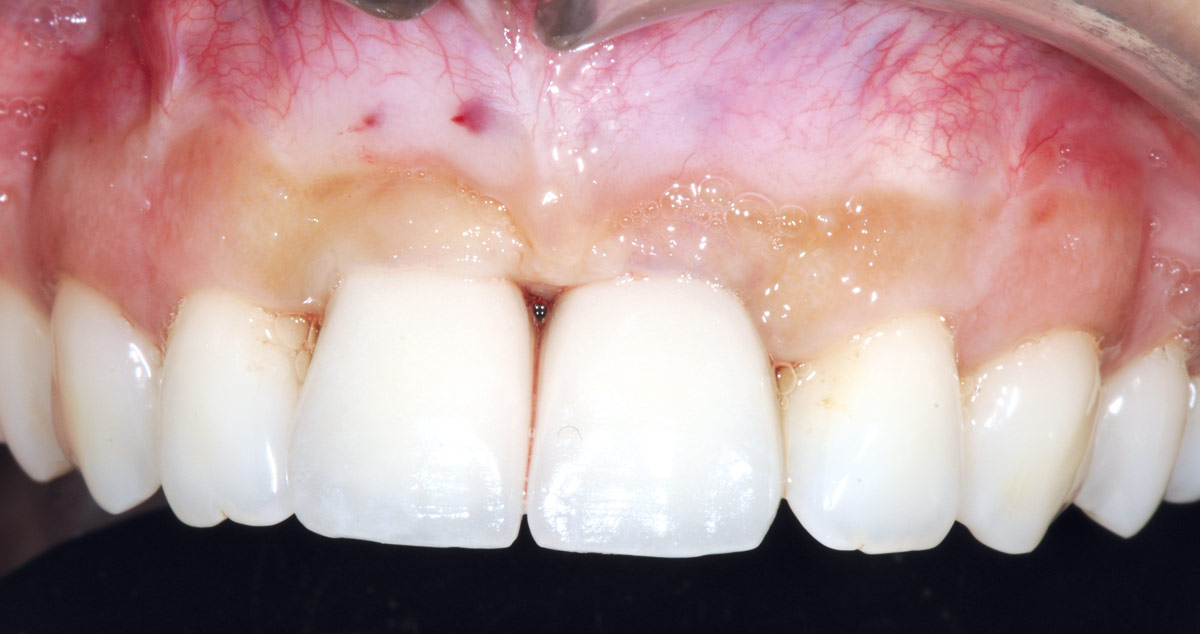

1/26 - Initially bridge retained incisorsBone augmentation in aesthetic zone with maxgraft® bonering - Dr. A. Patel

Initially bridge retained incisors